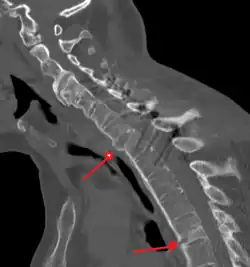

-

Lateral X-ray of the mid back in ankylosing spondylitis -

Lateral X-ray of the neck in ankylosing spondylitis -

CT scan showing bamboo spine in ankylosing spondylitis -